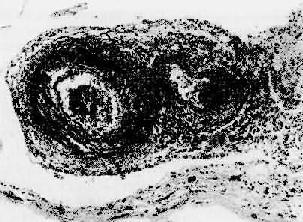

结节性多动脉炎

图4-13 结节性多动脉炎

两个动脉壁的各层都有炎性细胞浸润,外膜尤为显著。中膜发生纤维素样坏死